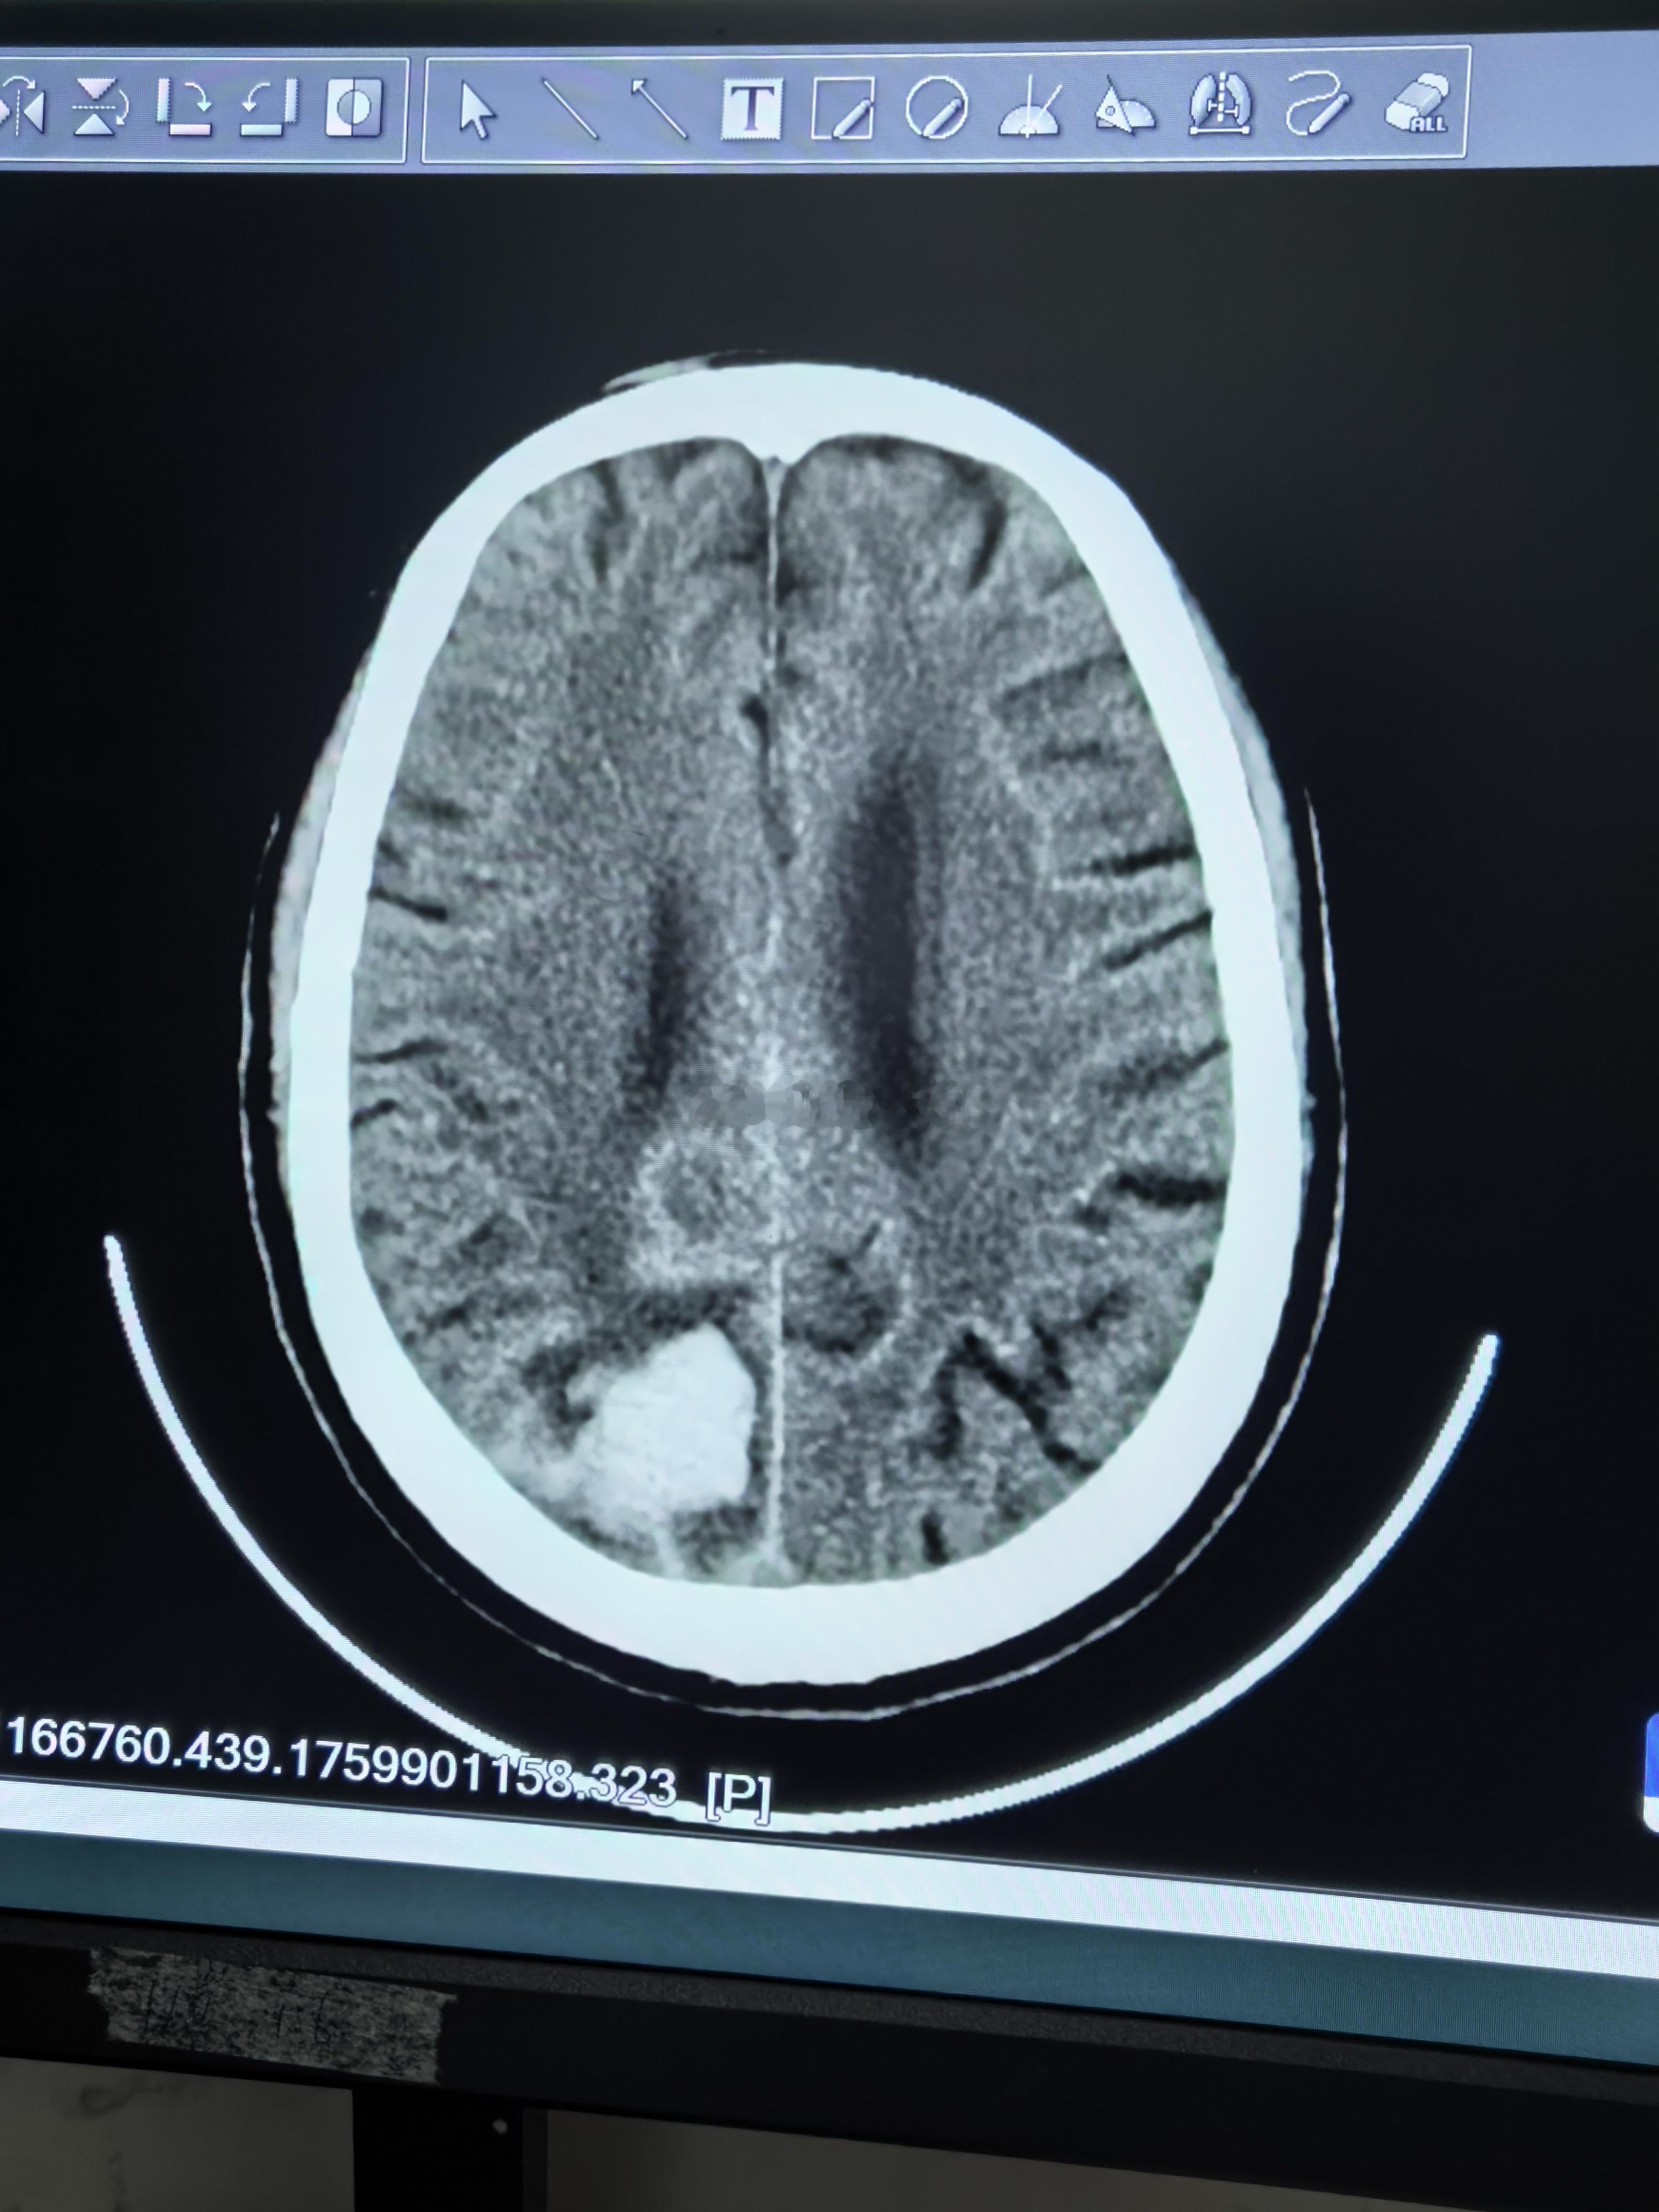

天气一冷,我们科走廊又加床了。

下午门诊临近下班来了个患者,安排了检查,脑出血。